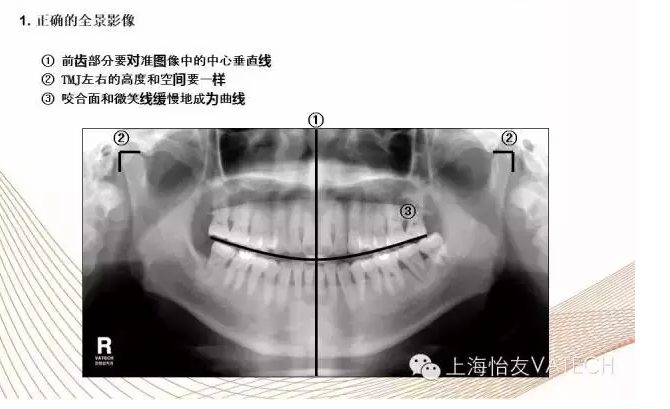

- 影像專題課二:口腔影像閱片基礎(chǔ)(二)正常影像

- 影像專題課一:口腔影像閱片基礎(chǔ)(一)設(shè)備及方法